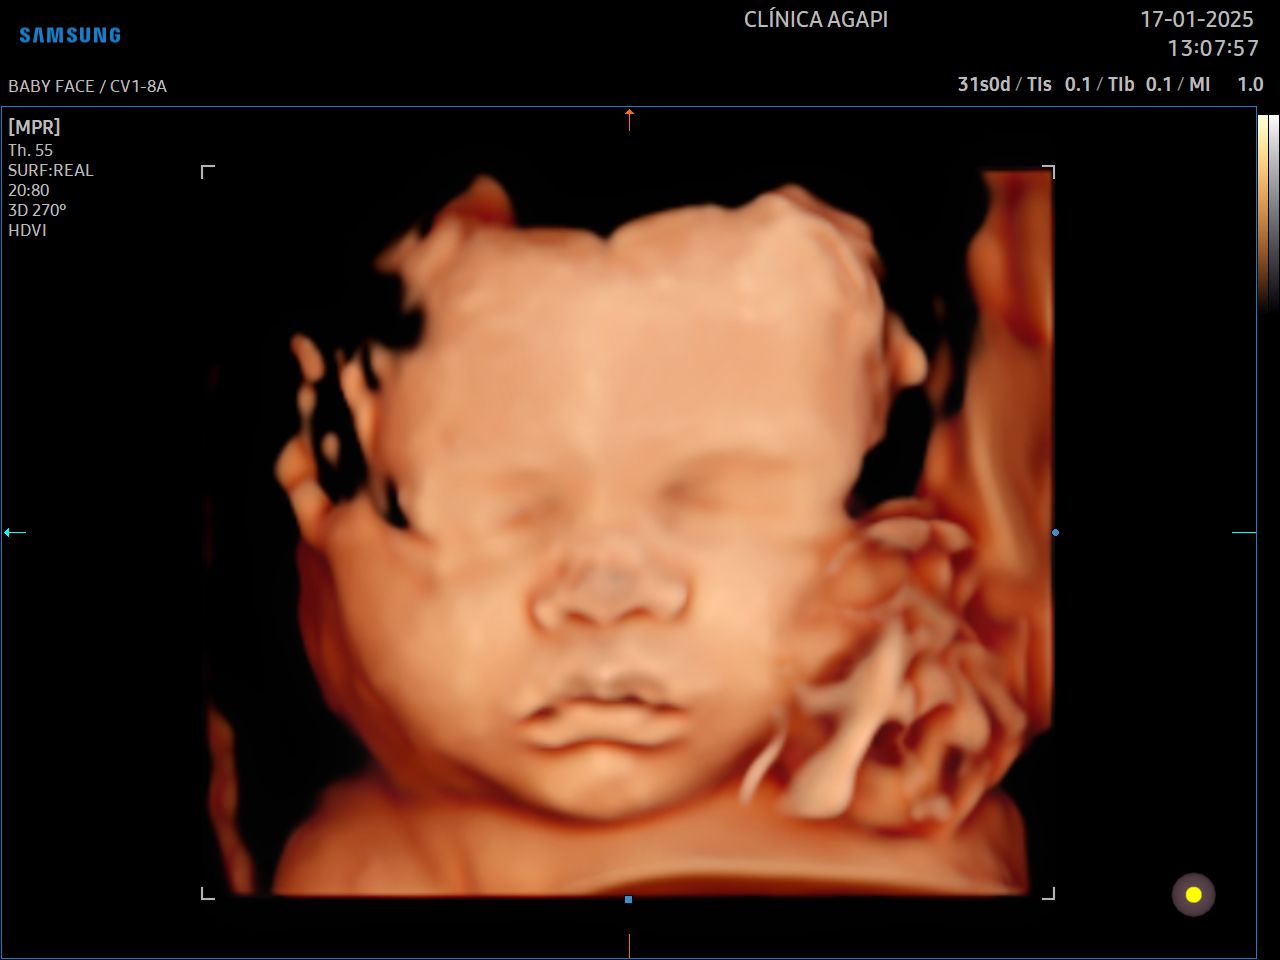

O 3D é realizado com um transdutor especial que reconstrói a superfície adquirida em uma imagem de 3 dimensões, estática. Já o 4D permite visualizar essas imagens com movimento do bebê em tempo real. Com a tecnologia HD live temos a cor do feto que dá a impressão da cor da pele.

A capacidade de aquisição de uma boa imagem tridimensional (3D/4D) depende de vários fatores, dentre eles: quantidade de líquido amniótico, posição fetal, inserção placentária, espessura do tecido celular subcutâneo materno, número de fetos, padrão de movimentação fetal durante o exame, dentre outros fatores que devem sempre ser individualizados.

Aqui na AGAPI, em qualquer exame - e se o bebê colaborar, sempre vamos fazer esses registros incríveis que a mamãe tanto ama.